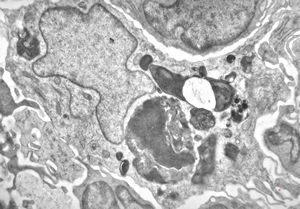

F, 85y. | Merkel cell tumor